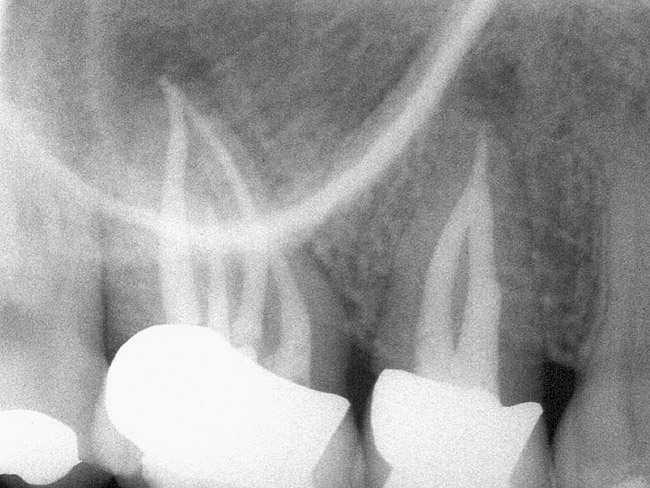

Figure 3a  Tooth No. 14 A #15 Hedstrom file had been separated in the distobuccal canal of tooth No. 14.

Figure 3a

Figure 3b  Although an attempt to retrieve the separated file was done during conventional treatment, it could not be removed because of the location of the file and the curvature of the canal.

Figure 3b

Figure 3c  A microsurgical retrieval became necessary. The fragment was located and removed.

Figure 3c

Figure 3d  The distobuccal root was subsequently sealed with MTA. The 1-year recall radiograph shows complete bone healing around the distobuccal root.

Figure 3d